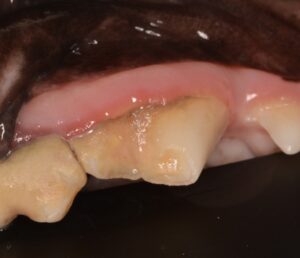

5歳のビションフリーゼさん。奥歯が黒く見えるという主訴で来院されました。幸い虫歯ではありませんでしたが、左右の上顎第四前臼歯がどちらも破折していることが分かりました。また、左右で破折の状態が異なりました。

右第四前臼歯:単純性歯冠破折

歯の中の神経は露出(露髄)していませんでしたが、エナメル質がなくなり、象牙質が露出した状態でした。